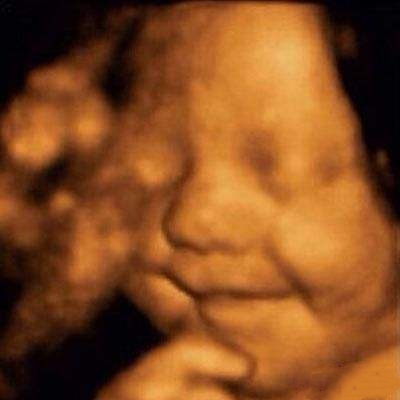

其实,关于胎宝宝在肚子里微笑,类似的报道并不少见,很多妈妈反馈过做四维时看到宝宝笑的样子,国外媒体也经常报道类似的新闻。

2003年,英国《卫报》报道,科学家用4D超声波成像系统拍到了26周宝宝微笑的图片。

2018年,英国《每日邮报》报道,一对夫妇在做四维彩超时发现宝宝咧嘴微笑,让父母感到喜出望外。

见诸各大网站的3D胎儿图像,也展示了胎儿在19周时微笑的模样,栩栩如生,惹人喜爱。